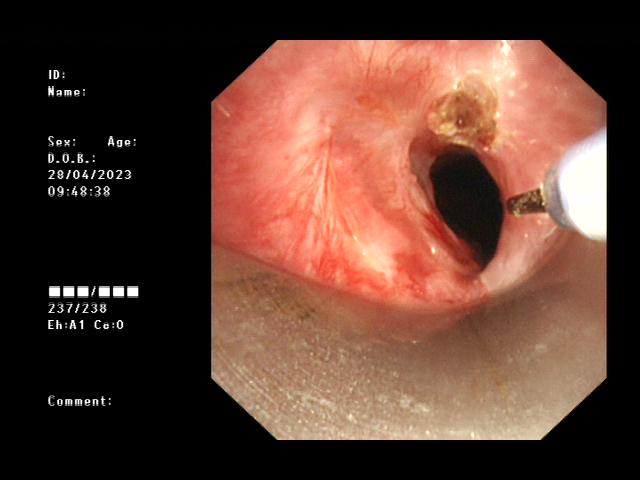

经过术前的充分准备,患者在全麻下,用可弯曲支气管镜引导插入法插入硬镜,通过高频电刀放射状切开狭窄环,再予气道球囊扩张器扩张气道置入硅酮支架,并置入喉罩复苏,最后成功为患者实施硬质支气管镜技术。术后,患者气道通畅,无呼吸困难、气促等症状出现,对比术前生活质量得到明显改善。

球囊扩张气道